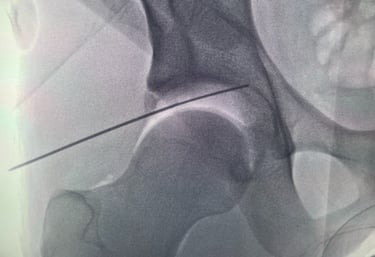

Galería Médica

Imágenes de procedimientos y técnicas en cirugía de cadera.